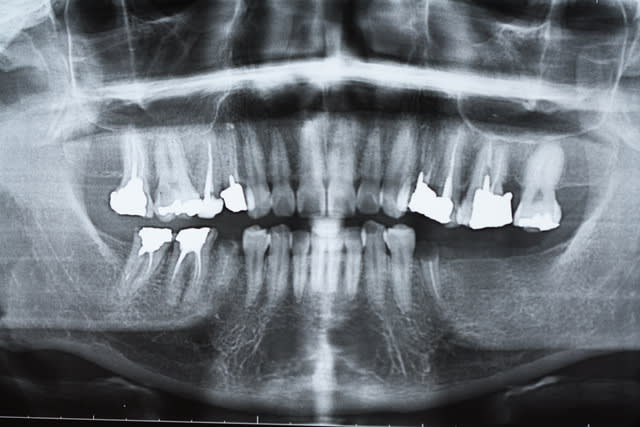

plus d'une heure pour essayer de sauver ces 37 et 38...

mais etait ce vraiment suffisant? cicatrisation possible?

60 mn environ pour ces 2 là, le canal mv2 augmente le temps d'exéctution de 15 à 30 mn surtout si l'entrée est proche du mv1. Il n'y a pas photo entre la préparation canalaire du r25 VS f2 protaper.

40 mn canal palatin xxl !

Merci. 3 récapitulations s1-r25 pour arriver au bout. je n'ai jamais vu un instrument aussi efficace que le r25, on croirait une ampliation au 50, en insistant un peu il n'y a plus de racine ! )))

Ton matériau d'obturation est confiné dans l'endodonte, je ne vois pas de dépassement de gutta, tes cones sont bien ajustés, je ne vois pas de déchirement apical.

+1 l'interet c'est de faire partager ses astuces. Je ne prétend pas etre le roi de l'endo mais en ce qui me concerne j'ai trouvé une séquence qui me permet d'avoir des résultats reproductibles en un minimum de temps. Une autre 40 mn.

avec quelle technique d'obturation obtiens tu de si belles images radio?

La plus simple lentulo scellement monocone, tuck back à l'apex quand même.